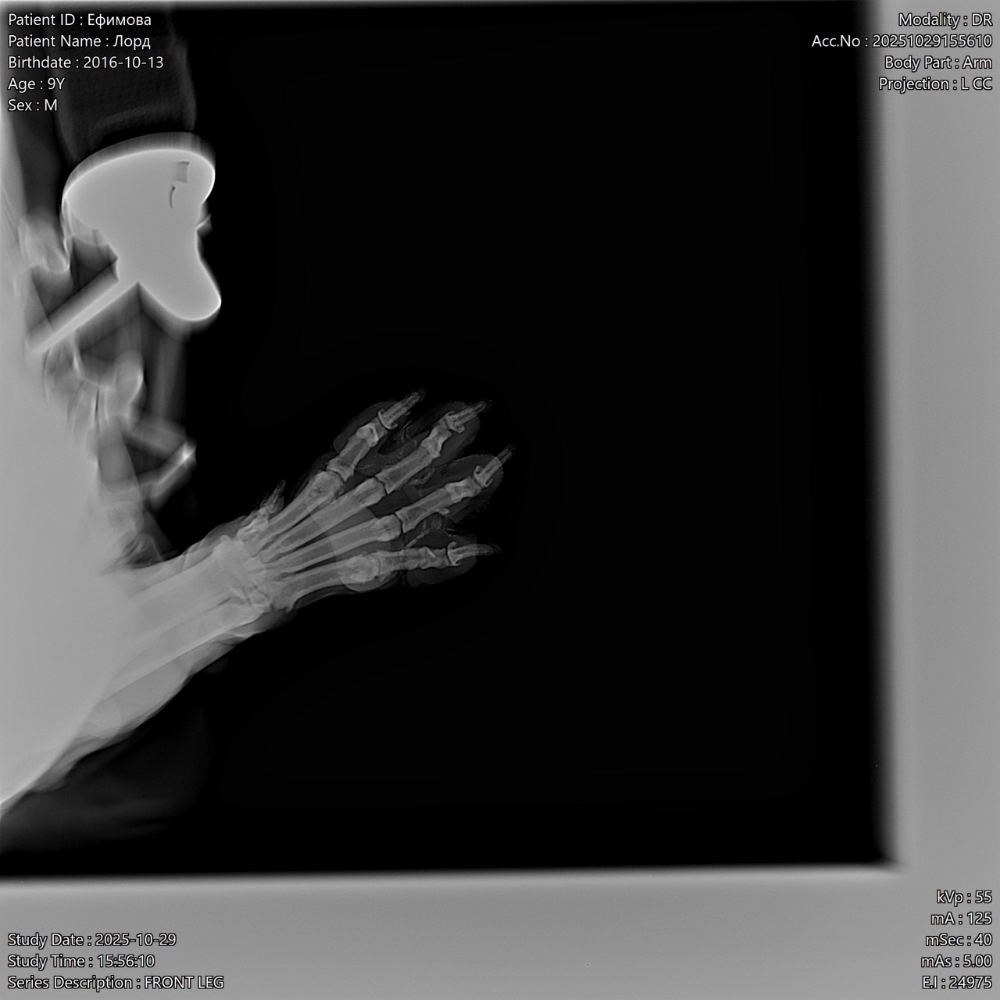

Всем привет, у меня собака лабрадор мальчик Лорд 9 лет. С детства на натуралке, месяц назад появилась шишка на лапе,  воспалилась лапа , которая у него по-видимому ноет и он ее разлизывает.

Ему сделали рентген ( фото прилагаю)

Он на лапу бывает хромает , и плюс еще дерматит межпальцевый пошел. Лапы после прогулки начала обрабатывать хлоргексидином.

Врачи толком ничего не говорят , что это может быть , подскажите пожалуйста, что это может быть(